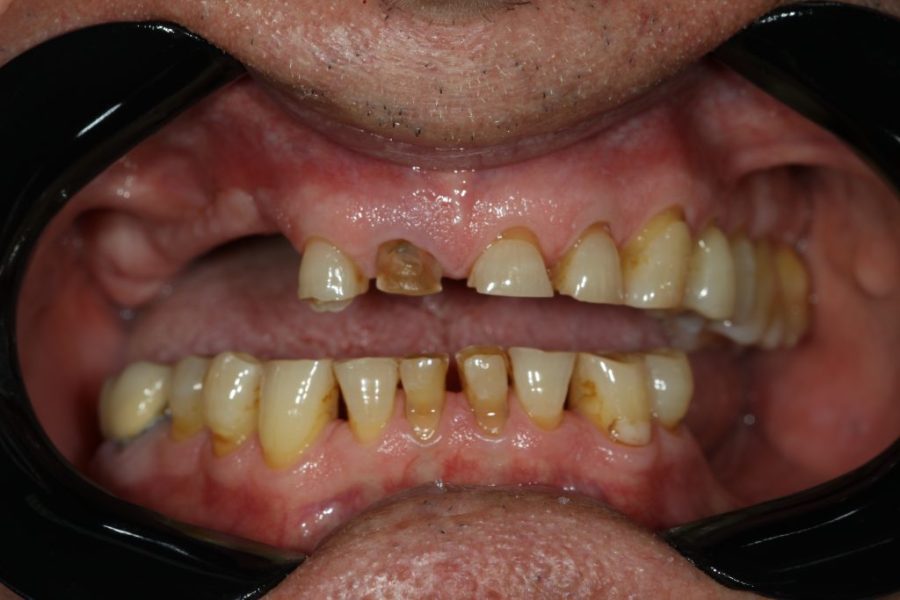

Henry’s Story: A Full Smile Makeover

Henry’s broken teeth were impacting his confidence. With a combination of root canal therapy, laser gum surgery, crowns, and dentures, we restored his smile over four weeks. Now, his family and grandchildren are thrilled with his transformation.